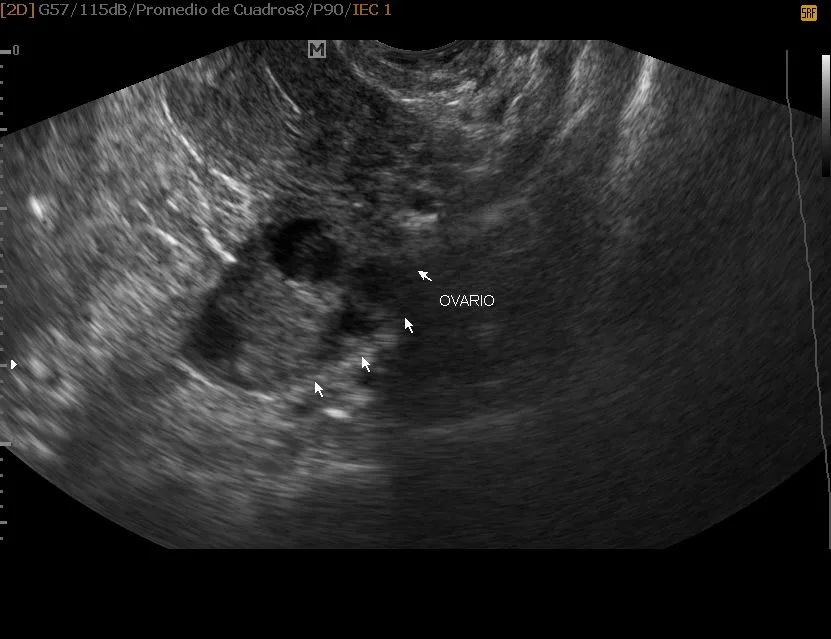

ULTRASONIDO PARA SEGUIMIENTO FOLICULAR

Se realizan ultrasonidos periódicos para evaluar los genitales internos y las variaciones que ocurren a lo largo del ciclo ovulatorio en una mujer en edad fértil. Esto nos permite verificar si la mujer ovula o no, y el momento exacto en que esto ocurre.